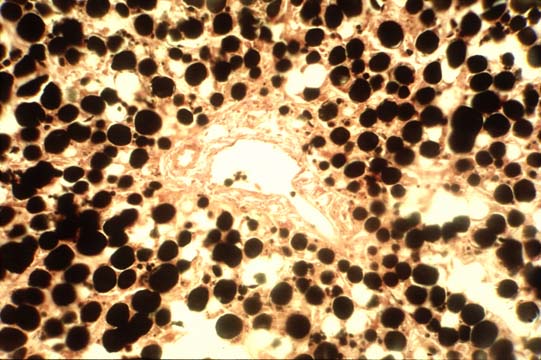

Fig 39 - Fat droplets with osmium

Teroxide fixation

& H&E stain.